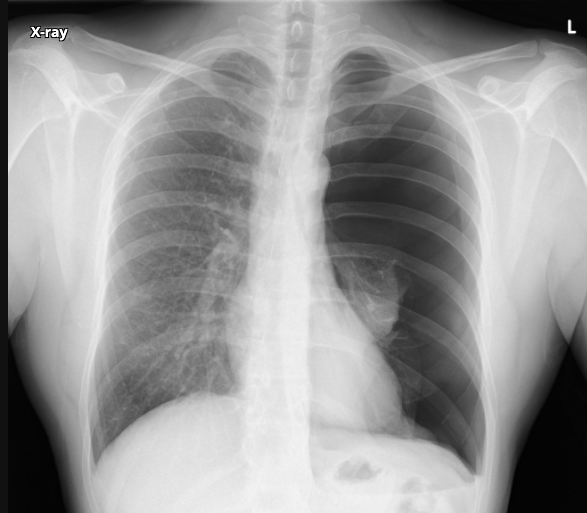

whats wrong here?

how can you tell?

pneumothorax